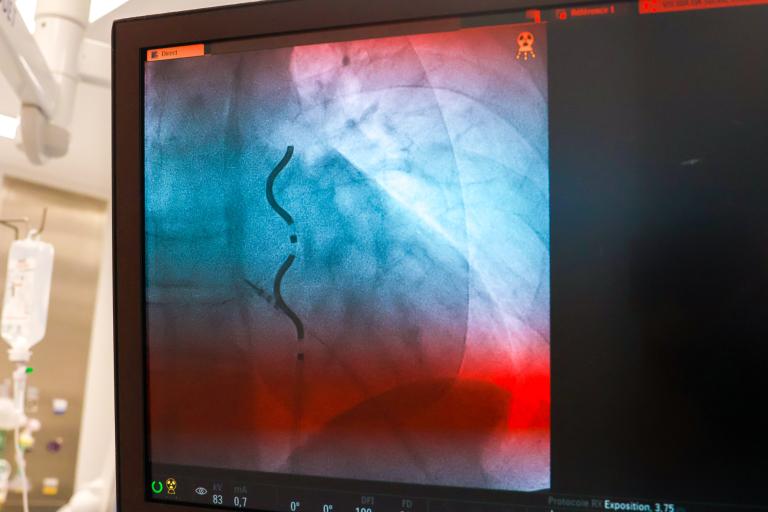

Le défibrillateur Aurora™ EV-ICD s’inscrit dans cette continuité thérapeutique tout en apportant une innovation majeure. Conçu pour offrir les bénéfices des DAI transveineux conventionnels, il se compose, comme eux, d’un boîtier et d’une sonde implantés au cours d’une seule procédure. Sa spécificité réside toutefois dans le positionnement de la sonde : celle-ci n’est ni placée dans le cœur ni dans le système vasculaire.

Implanté sous l’aisselle gauche (région médio-axillaire gauche), le boîtier est associé à une sonde de défibrillation positionnée sous le sternum par une approche mini-invasive. Ce positionnement extravasculaire vise à réduire les complications à long terme pouvant être associées aux sondes transveineuses, notamment l’occlusion des vaisseaux (rétrécissement ou obstruction veineuse), les fractures de sondes et le risque d’infections (endocardites infectieuses).

Le défibrillateur Aurora™ EV-ICD est implanté sous l’aisselle gauche et associé à une sonde extravasculaire Epsila EV™ MRI SureScan™, positionnée en dehors du cœur et des vaisseaux.